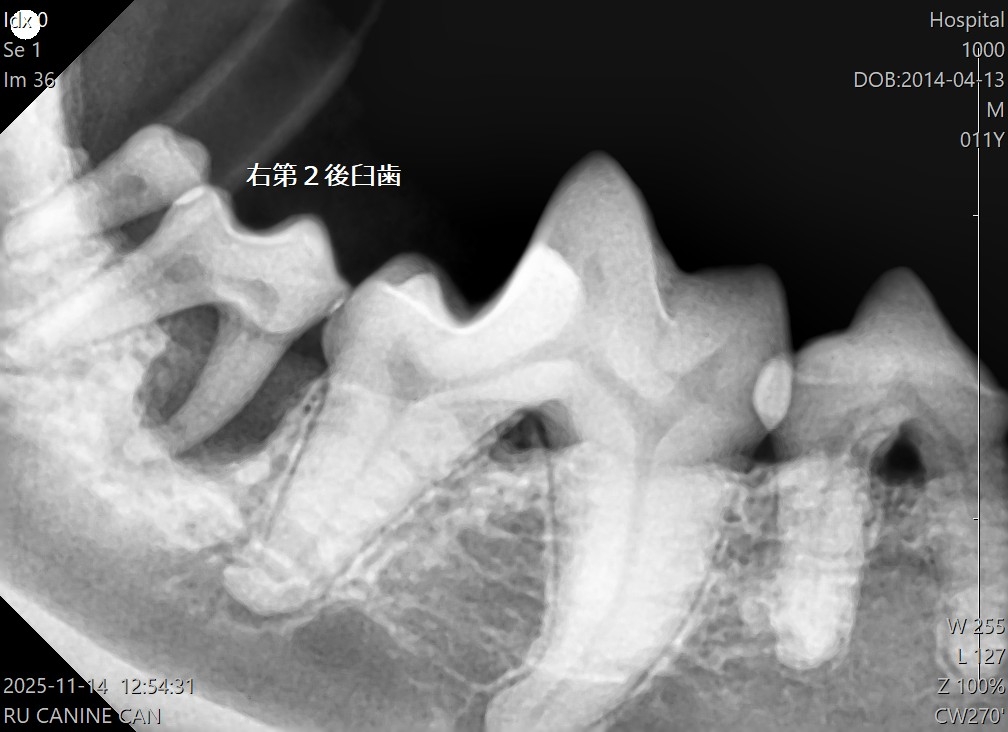

歯周ポケットの確認や歯科レントゲン撮影は、口腔内にブローブを入れるため 基本的には術直前に全身麻酔下で行います。

Lちゃんの場合歯周病の進行が著しく、既にぐらつきがあるもの 外見ではわからなかった歯根の周りの顎の骨が溶けている部分もレントゲンで確認できました。

今回は抜歯が必要と判断した場所にはその後、歯肉縫合を行いました。残った歯の歯石除去、歯周ポケットの洗浄、抗菌剤注入、研磨を行いました